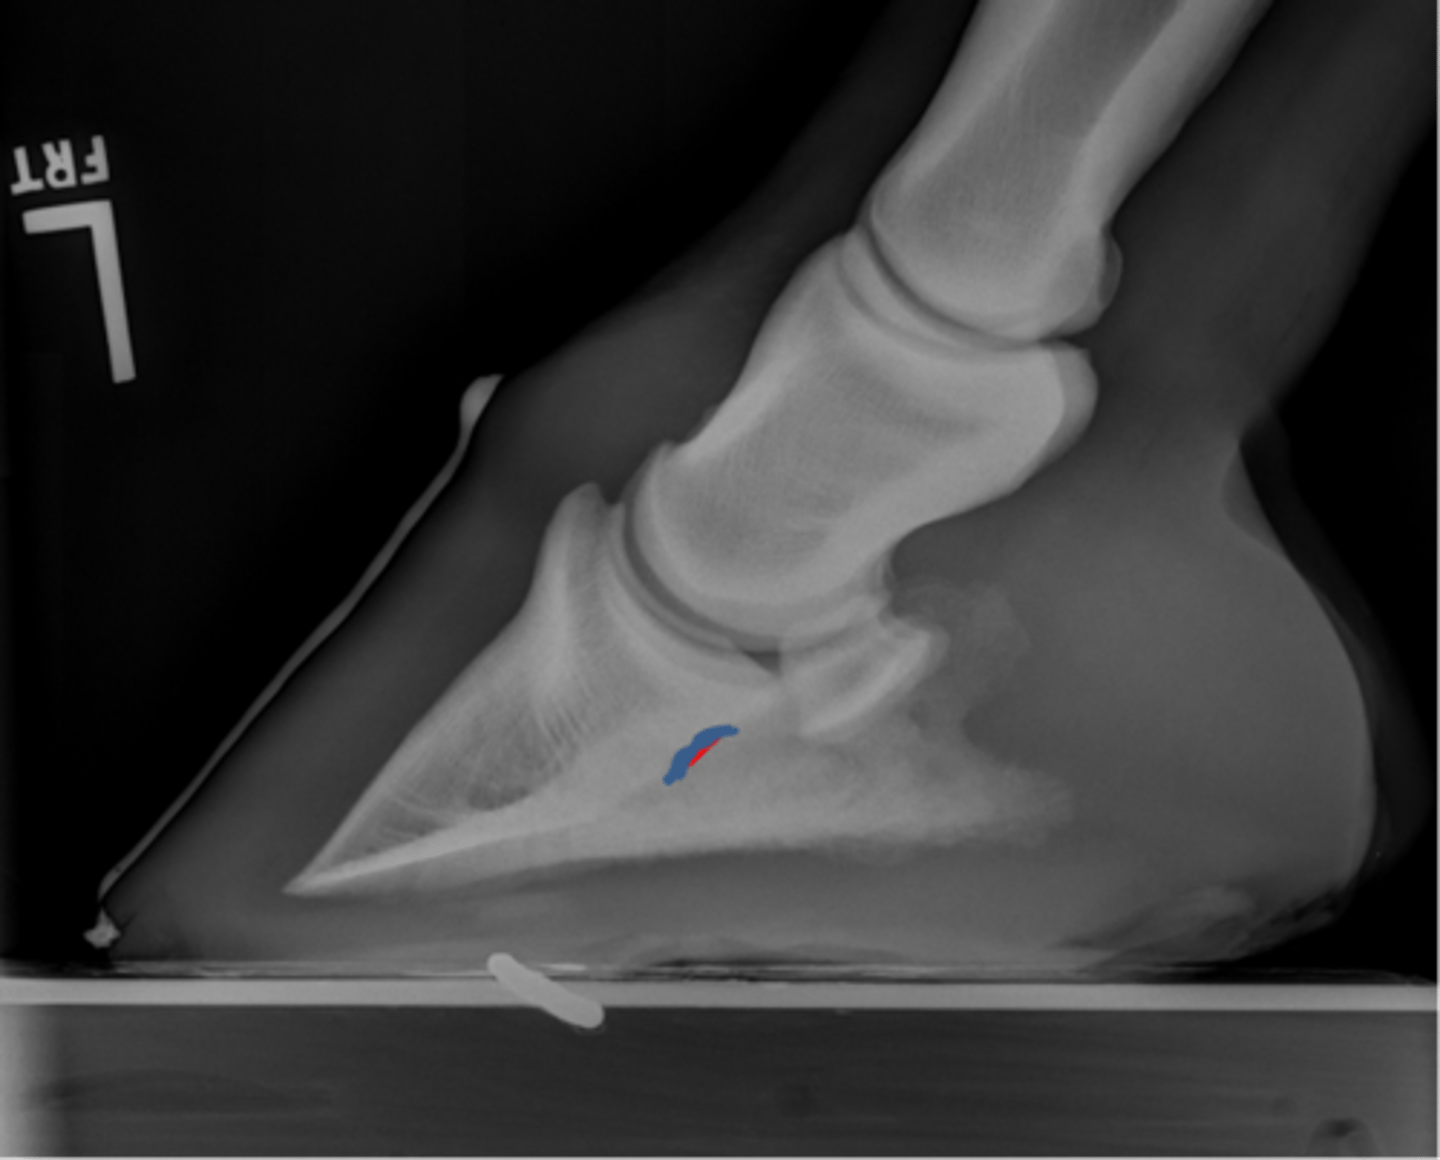

Coffin bone (P3)

Palmar process of P3

Extensor process of P3

DDF

Navicular bone

Coffin joint

Short pastern (P2)

Upright pedal or high coronary

What view is this?

Coffin bone

Navicular bone